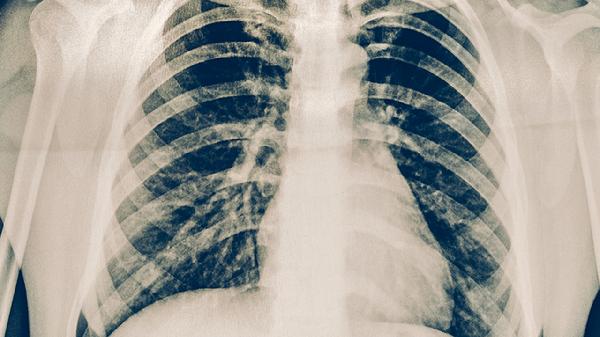

胸透通过X射线成像观察肺部结构,对直径较大的中央型肺癌或伴有明显肺不张、胸腔积液的晚期肺癌有一定检出能力。这类肿瘤通常已超过3厘米,可能伴随纵隔淋巴结肿大或肋骨破坏等典型征象。但胸透分辨率有限,对小于1厘米的肺小结节、磨玻璃样病变或位于肺尖、脊柱旁等隐蔽部位的病灶识别困难,而这些往往是早期肺癌的表现形式。胸透还存在前后组织重叠的局限性,可能导致20%以上的漏诊率。

低剂量螺旋CT能发现2毫米以上的微小结节,对早期肺癌的检出率是胸透的4-10倍。国际肺癌筛查研究证实,每年接受低剂量CT检查的高危人群,肺癌死亡率可降低20%。对于长期吸烟、有肺癌家族史或职业暴露史的人群,建议将低剂量CT作为常规筛查手段。胸透更适合作为肺部感染、气胸等急症的初步检查方式。